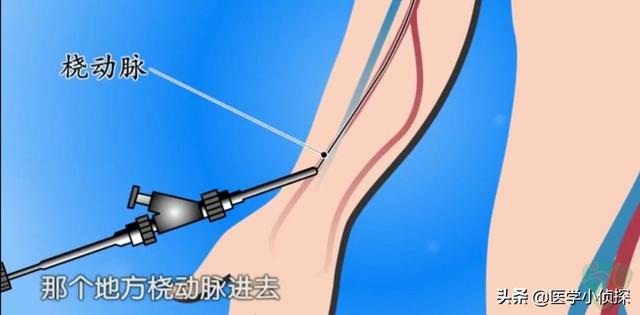

ステップ1、パンク。末梢動脈を見つけ、この動脈から穿刺を行うが、最も一般的な選択は、手の付け根か太ももの末梢動脈を選択することである。

ステップ2、チューブの挿入。その末梢血管開口部からシースを挿入し、適切なサイズのシースを選択してガイドワイヤーを進め、冠動脈開口部付近の心臓までゆっくりと送り込む。